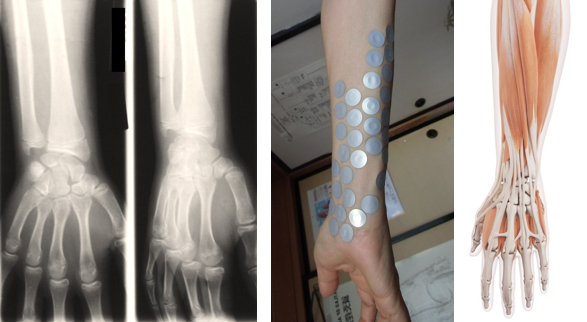

写真左は手首のレントゲン写真です。(骨の状態が分ります)

真ん中は手首の実際に痛い所を確認しながらパッチを貼って調べた写真です。

手首には色々な筋肉があり、これら筋肉の損傷が痛みの原因になります。

多くは仕事やスポーツでそれらの部分にある筋肉を酷使しているのが直接的な原因です。